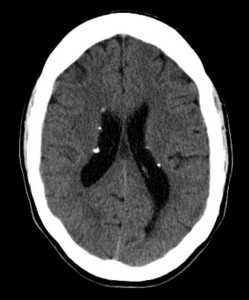

Наиболее типичными нарушениями в головном мозге являются корковые туберсы и субэпендимарные узлы. Туберсы могут быть как единичными, так и множественными, располагаются в виде выступов над единичной или прилегающими бороздами коры, расширяя их. Субэпендимарные узлы локализуются в стенках боковых желудочков и, реже, в стенках III и IV желудочков мозга. У новорожденных субэпендимарные узлы редко бывают кальцифицированными. По мере роста ребенка наблюдается постепенное отложение кальция в субэпендимарных узлах.

Субэпендимарные кальцификаты и корковые туберсы на КТ головного мозга ребенка с туберозным склерозом

На стенках боковых желудочков выявляются субэпендимные узлы, которые часто накапливают кальций. Если эти узлы располагаются вблизи отверстия Монро , то эти узлы принято считать астроцитомати. Субэпендимальная гигантоклеточная астроцитома (СЕГА) распологаются вблизи отверстия Монро ( обращаю ваше внимание что данный термин используется для образований размерами свыше 5 мм). Для правильной оценки размеров астроцитом необходимо использовать контрастное усиление. Оценка размеров СЕГА очень важна для оценки динамики течения заболевания, поэтому в протоколе исследования необходимо указывать не только три максимальных поперечных размера образования но и считать объем опухоли. Расчет объема производится по формуле определения объема эллипсоида (задается следующей формулой: 4/3pi*abc). Оценка размеров производится только на контрастных последовательностях.

КТ головного мозга при туберозном склерозе. Видны кальцинированные субэпендимальные узелки в стенках боковых желудочков.